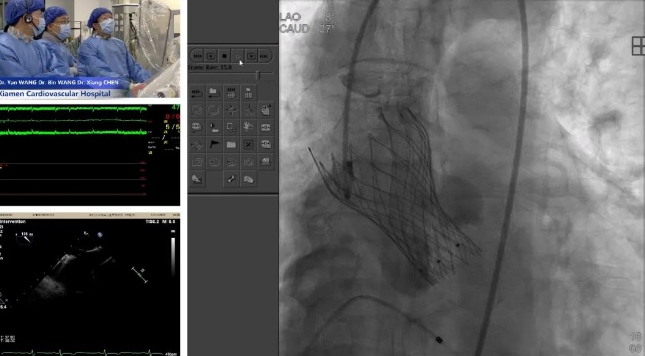

2025-04-30人民网 | 主播福利 运用国产新型胸主动脉覆膜支架开展手术 -

2024-12-18一天两场国际手术直播,主播福利 助力国产创新器械出海 -